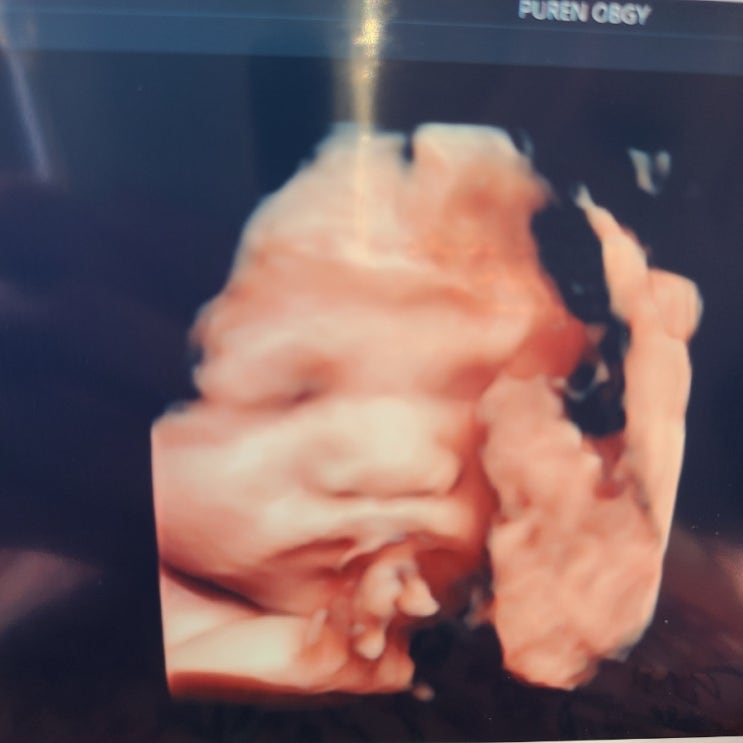

둘째 대공개 D-1

토핑 없는 타코야끼와의 첫 만남은 아직도 생생하다. 떨림과 두려움 가득 안고 집에 데려왔던 날도 기억한...